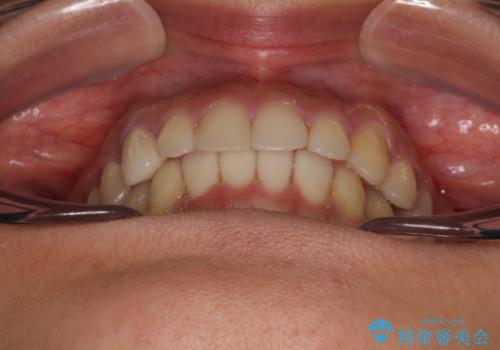

- 1年4ヶ月

しっかりとマウスピースを装着してくださったおかげで、スムーズに治療を終えることができました。

矯正治療途中で右下奥歯の虫歯治療を近医で行ったようで、既に神経が失活していたと合わせて矯正治療後に補綴治療を行う予定です。